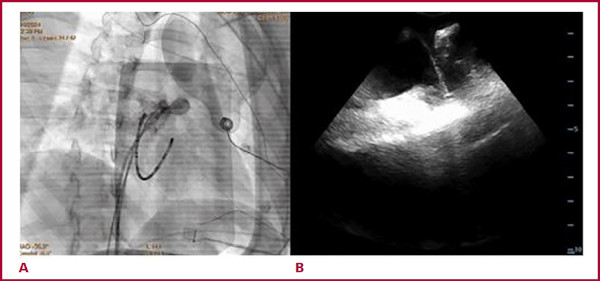

A los 9 meses la paciente continuaba sintomática, refractaria a múltiples esquemas de tratamiento médico. En el ECG Holter control, episodios de taquicardia a 177 lpm. Se solicitó angiotomografía cardíaca que evidenció OD de base ancha con su extremo superior en continuidad con la AD. Se procedió con nueva ablación. Con sistema de navegación tridimensional CARTO 3 System y catéter Pentaray® se realizó reconstrucción y mapa de activación de AD, vena cava superior y OD. Se continuó con angiografía de la OD (Figura 1A), la cual se observaba lobulada, de base ancha y con presencia de un aneurisma, de base angosta y cuerpo de alrededor de 3 cm de diámetro, móvil con los latidos. Con utilización de ecocardiografía intracardíaca (Figura 1B) se confirmó dicha anatomía y se guió la ablación. Se realizó mapa de precocidad desde la base del aneurisma hacia el interior, y se evidenció mejor precocidad dentro del mismo (-45 ms). Con catéter irrigado externo Smarttouch SF® se realizaron 5 aplicaciones en el interior del aneurisma, sin lograr cortar la taquicardia. Se procedió luego a completar aplicaciones con catéter Freezor™ Xtra (-80°C) durante 240 segundos en dicha zona, sin evidencia de corte de la taquicardia. Finalmente, se decidió realizar aislamiento eléctrico del aneurisma con catéter de RF, y se evidenció el corte de la TA a los 8 segundos de esta última aplicación (Figura 2). Luego de 30 minutos de observación, se realizó protocolo de estimulación auricular y desde el interior del aneurisma, sin inducción de taquicardia.